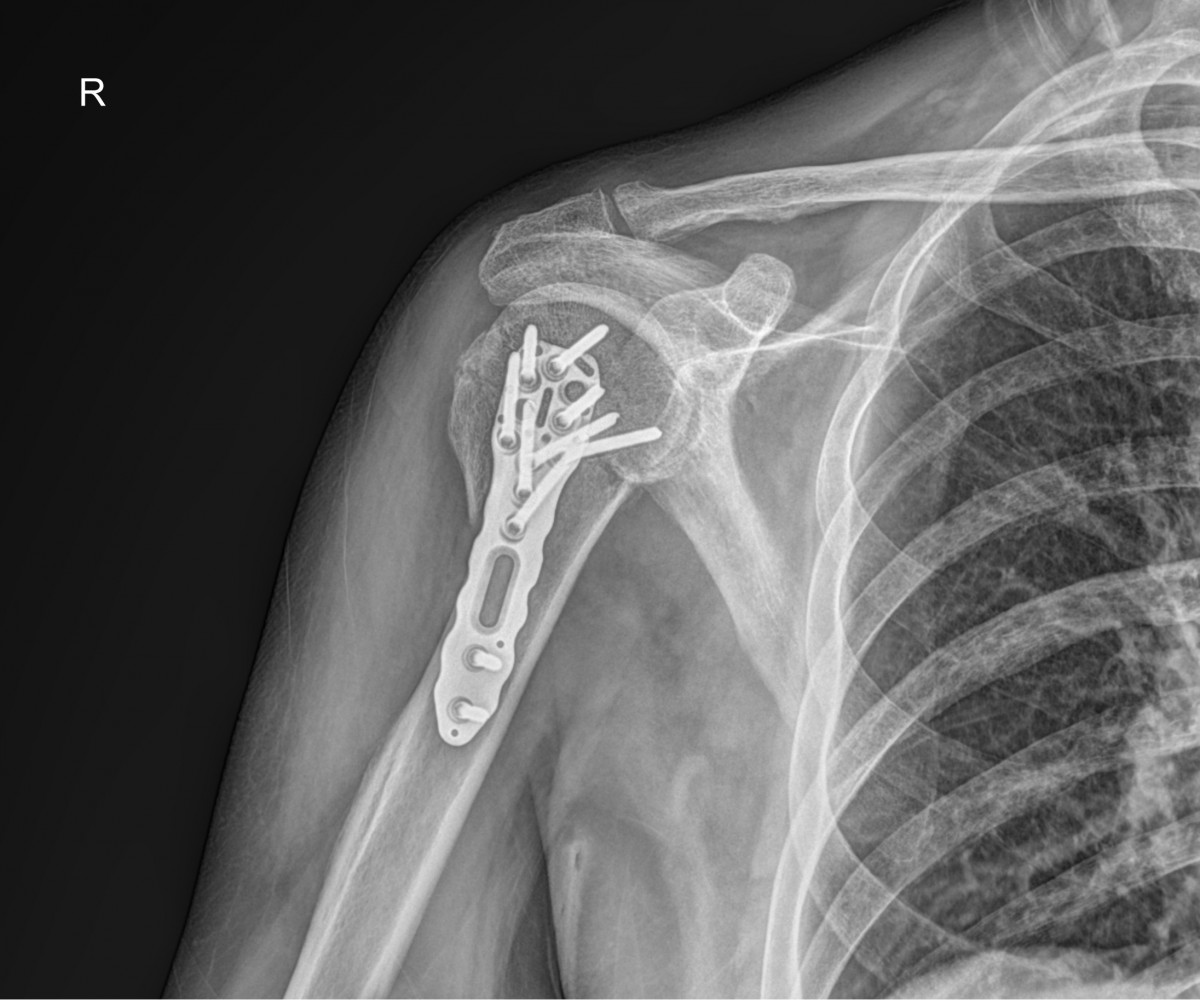

이재상원장님 어깨 골절 수술 박용O 환자

dae765e4d9ac96aee867c9d6292d8784_1758002687_5457.jpg